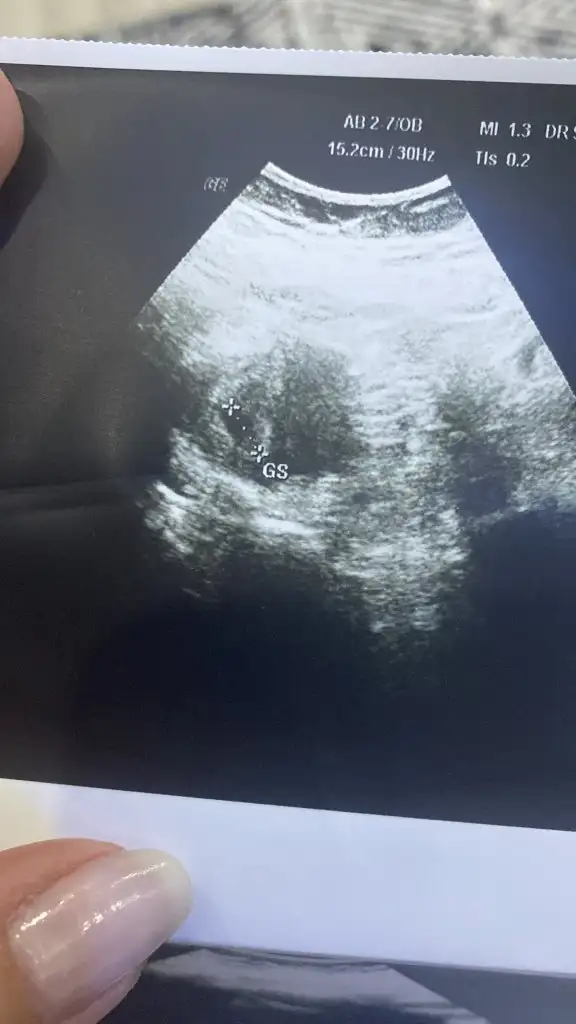

Gebeliklerd3 oluyor bende tansiyon düşüklüğü 6 ya kadar düşerTansiyonunu ölçtün mü, benim de baş ağrım var ama normalde migrenim de var hamileyken daha fazla etkiliyor. Hamilelikte düşük tansiyon iyi diye biliyorum ama hayatı felç edecek duzeydeyse doktoruna bı mesaj at istersen.